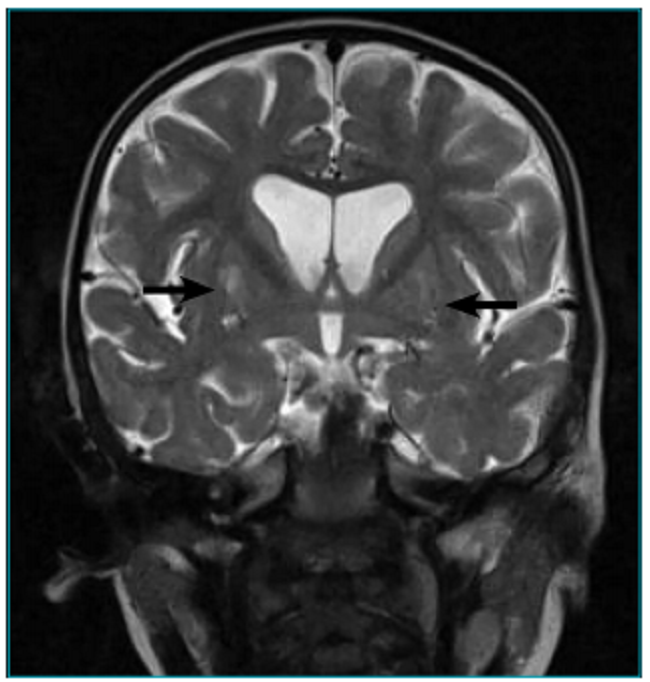

Perante a suspeita clínica e laboratorial de SL, deve ser realizada a ressonância magnética cranioencefálica (RM-CE). Os achados mais comuns, na imagem em T2, são as hiperintensidades focais, bilaterais e simétricas localizadas tipicamente nos gânglios da base (especialmente no putâmen) e/ou no tronco cerebral. Outras áreas frequentemente envolvidas são tálamo, substância nigra, núcleo rubro, tronco cerebral, cerebelo, substância branca cerebral ou medula espinhal.2,6,7,13 Essas lesões, evidentes tanto na imagem cerebral como nos estudos anatomopatológicos, são atribuídas à depleção de ATP, com consequente lactoacidose, congestão vascular, hipóxia e, finalmente, necrose. O envolvimento preferencial das regiões subcorticais é atribuído à maior vulnerabilidade à lactoacidose, que parece ser secundária ao seu suporte vascular, as arteríolas penetrantes.2,4,14

Nas imagens da RM-CE em T2, observava-se hipersinal lenticular, bilateral, expressando-se no putâmen e havendo dúvida em relação ao globo pálido esquerdo, o que sugeriu o diagnóstico de doença metabólica, principalmente na ausência de intercorrências durante a gestação e periparto (Figuras 1 e 2). Do estudo metabólico realizado, destacavam-se hipocitrulinemia de 5 µmol/L (normal 15 a 30 µmol/L) e hiperlactacidemia de 3,0 mmol/L (normal 0,5 a 2,2 mmol/L). A paciente apresentava piruvato sérico, amônia e cromatografia dos ácidos orgânicos normais. Executaram-se também potenciais auditivos evocados do tronco cerebral, eletrocardiograma e ecocardiograma, que não revelaram alterações. Foi avaliada por oftalmologista, revelando exame normal.